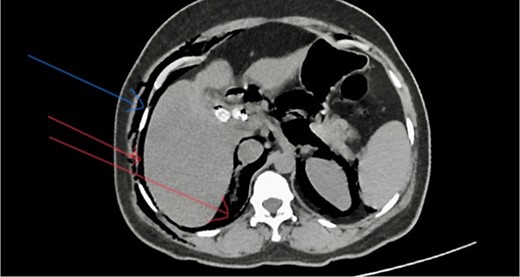

Post-ERCP NCCT abdomen shows pneumo-peritoneum (red arrow), pneumo-retroperitoneum, and subcutaneous emphysema (blue arrow)

She has undergone a semi-elective ERCP in a semi-prone position, under sedation with propofol target-controlled infusion. Major papillae identified with side viewing endoscopy. Guidewire was inserted into CBD, and a cholangiogram was done. It showed dilated CBD up to 1.3 cm, mild dilated hepatic ducts, and a large radiolucent area in the distal CBD (around 1.5 cm). Sphincterotomy was done with a sphincterotome, and the ampulla was dilated up to 1.5 cm with a balloon dilator. Then, a balloon retrieval was attempted and failed, probably due to a stone sticking to the CBD wall. Then, a mechanical lithotripter was used to break the stone, but it failed, damaging the instrument. During the procedure, her oxygen saturation dropped to 75–80%, and she developed surgical emphysema in the face, neck, and upper chest region. In addition, she developed abdominal distention as well. Immediately, she underwent CBD stenting with a 12-cm, 10 French Gauge double pigtail biliary stent and changed her position to supine. Then, she was intubated with rapid sequence induction, and a nasogastric tube was inserted and transferred to the surgical intensive care unit. Post-ERCP, non-contrast computed tomography (NCCT) of the abdomen and chest showed extensive pneumo-peritoneum and retroperitoneal gas with subcutaneous emphysema (Figs 2 and 3). There was no evidence of air leakage on NCCT and no clinical features of peritonitis on subsequent days. So she was managed non-surgically with nasogastric tube (NG), nil by mouth, intravenous fluids with intravenous antibiotics. Clear fluid was started after 24 hours slowly via NG.

Management of ERCP-related complications depends on the type of perforation and the patient’s clinical condition. Type 1 perforations are managed with surgical repair [15]. Type 2 perforations are mainly managed conservatively, but some cases with clinical findings of peritoneal signs and sepsis and those with retroperitoneal or peritoneal fluid on CT require surgical repair [15]. Type 3 perforations are usually managed conservatively. Type 4 perforations are also generally managed conservatively, as these are no actual perforations [6, 14] In this case, the patient developed surgical emphysema and abdominal distention suggestive of perforation. She developed respiratory compromise due to pneumo-peritoneum, and her oxygen saturation was dropped during the time of procedure. Therefore, the clinical diagnosis of perforation was made, and the patient was intubated and managed conservatively in the ICU during the post-ERCP period without any need for surgical perforation repair. Post-ERCP, NCCT showed extensive pneumo-peritoneum and retroperitoneal gas with surgical emphysema.